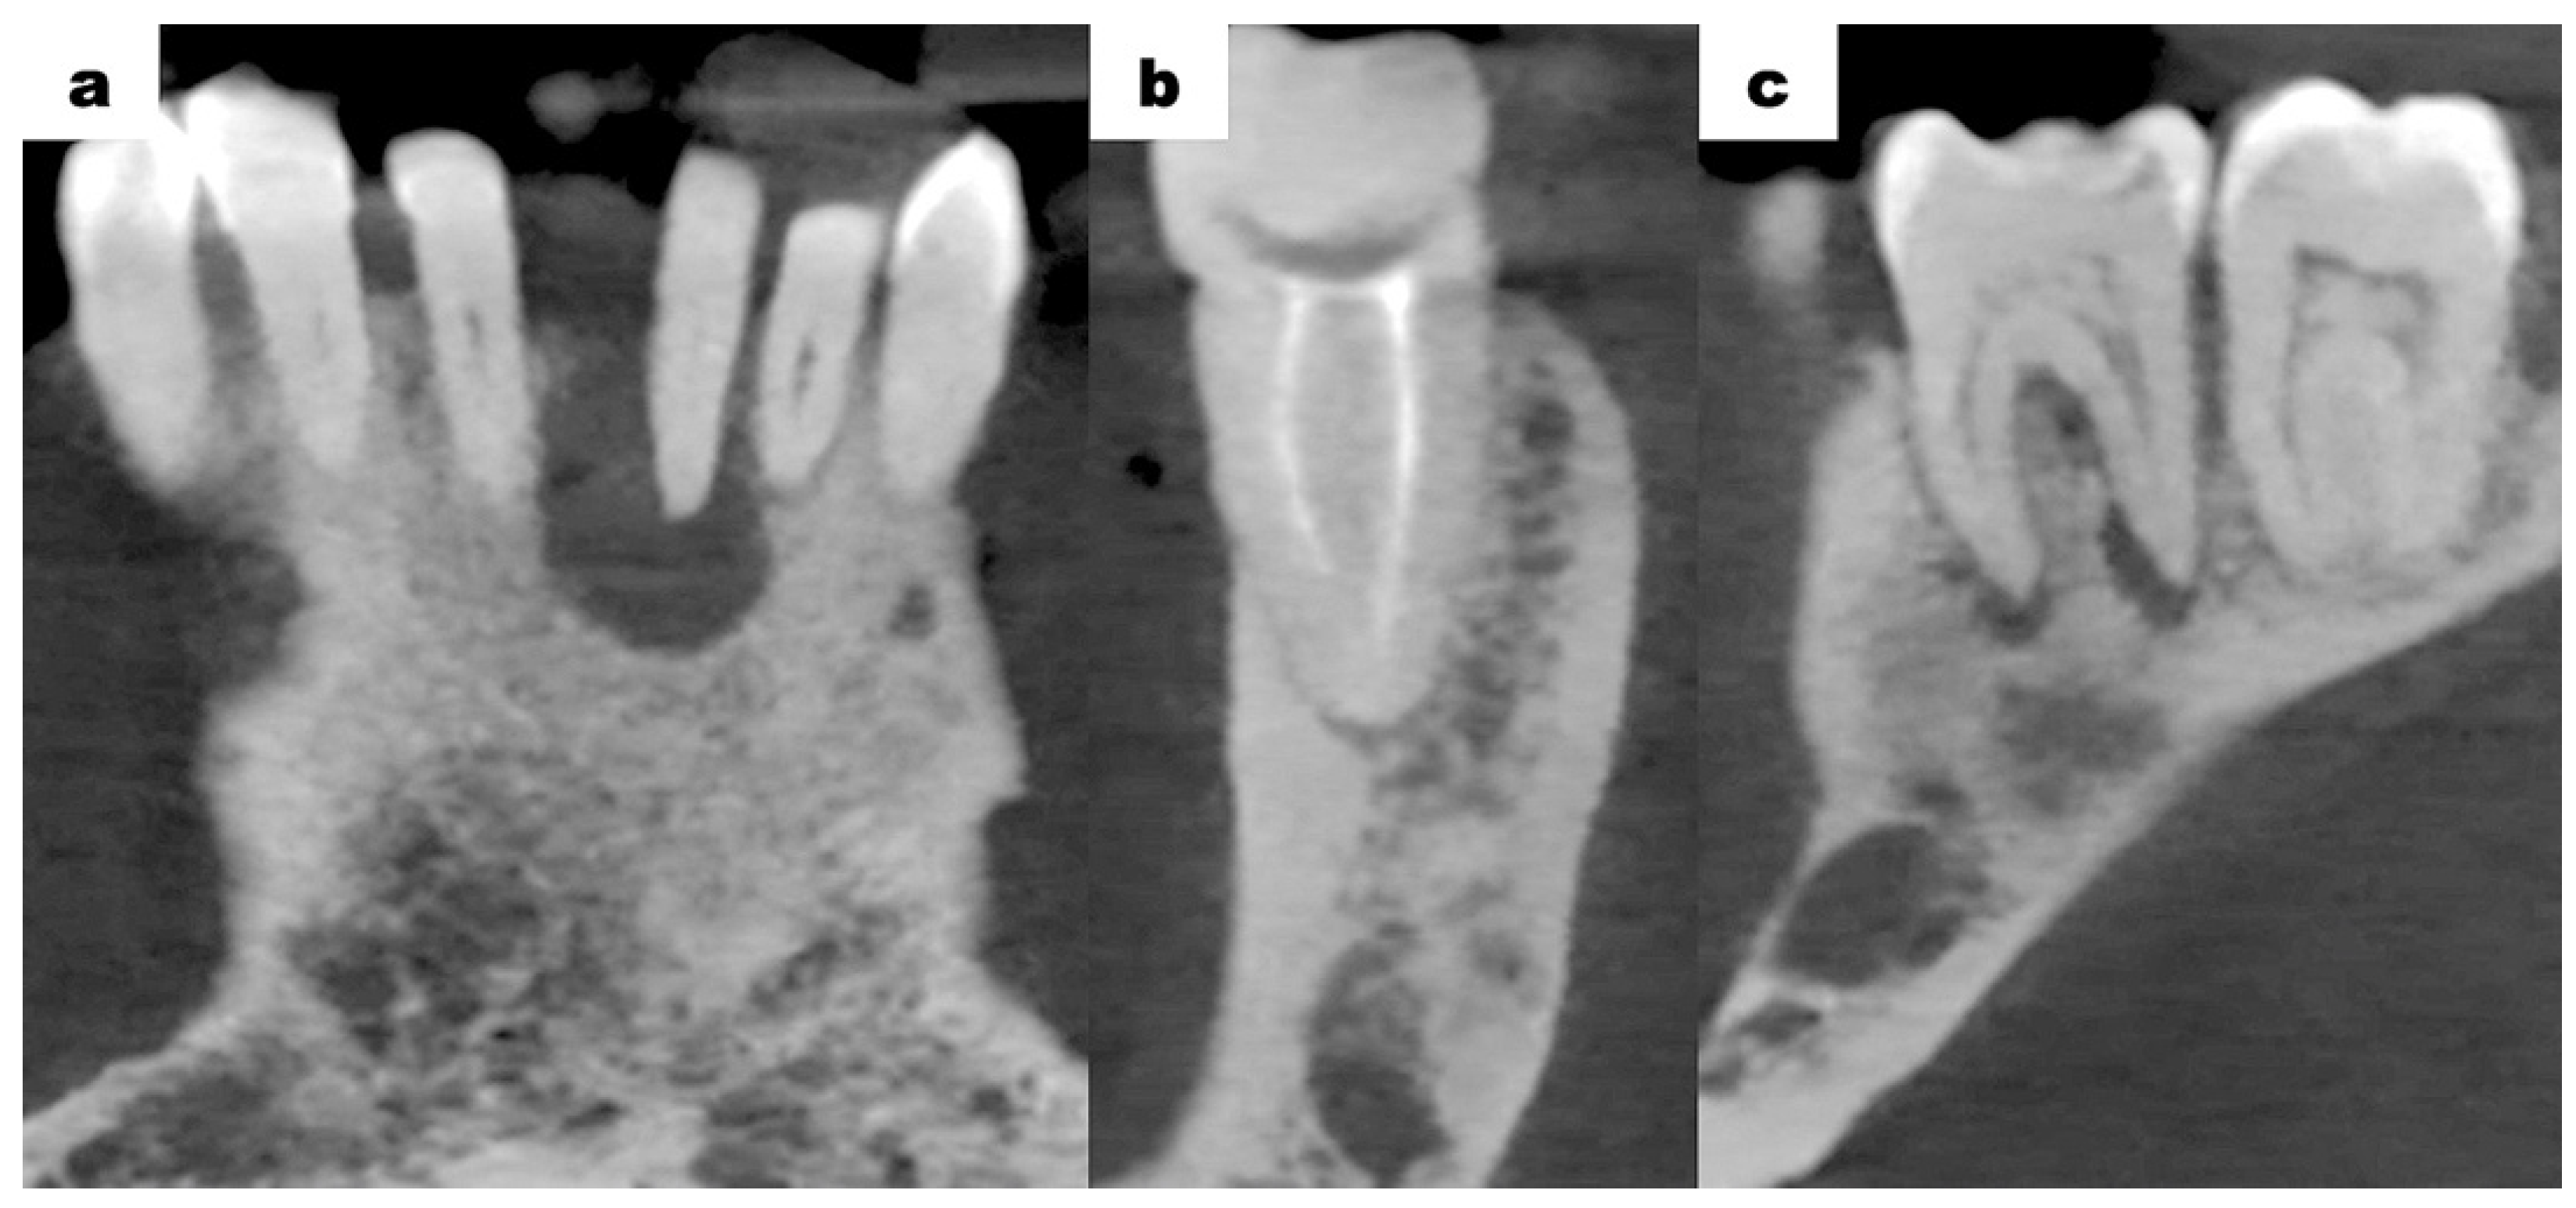

The treatment plan included the extraction of tooth 31, conservative removal of carious lesions, endodontic treatment, and oral hygienisation (oral hygiene management). The surgery was performed in the antibiotic shield under local anaesthesia using lignocaine 2% with noradrenaline in a hospital setting. Tooth 31 was removed entirely. There was no increased bleeding from the tooth extraction socket. The lesion was curetted and submitted for histopathological examination. The cavity was rinsed with a Metronidazole solution and sutures were placed. Postoperatively, the patient was given an antibiotic (amoxicillin 875 mg/clavulanic acid 125 mg) every 12 h for 7 days. A follow-up visit was scheduled after 7 days of uneventful healing. No postoperative complications were noted. The follow-up 7 months after the procedure showed a properly healed alveolus after extraction (Figure 6a,b).

The histopathological examination result of the periapical lesion was the purulent granulomatous tissue. Regarding the clinical and radiological examinations, which revealed extensive vascular changes, it was concluded that a simple procedure such as a tooth extraction could result in an extensive haemorrhage. No postoperative complications after extraction of tooth 31 were observed. The sutures were removed after 7 days of uneventful healing. The patient did not report any complications such as bleeding or inflammation.

Figure 6. (a,b): Intraoral photographs 7 months after the extraction of tooth 31.